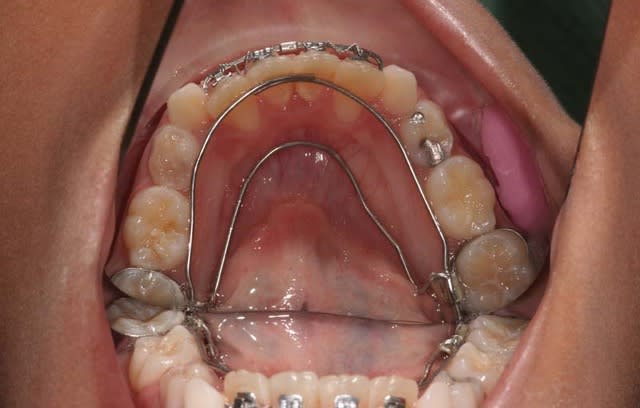

04/10/2009 à 17h13

1°) phase

Q.H. Sup.

Z.H. Inf.

à suivre

4 zekpha - Eugenol

5 crm6hv - Eugenol

6 a4j436 - Eugenol